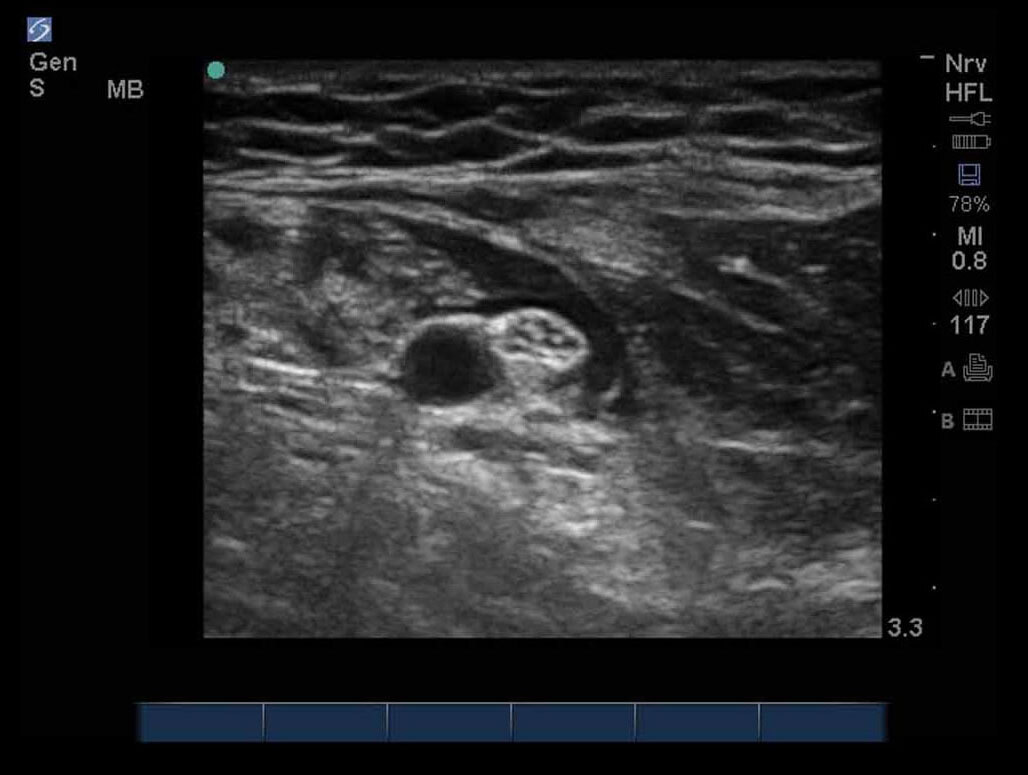

Median 2 Nerve Post Injection Image

M-Turbo: Median Nerve Post Injection.